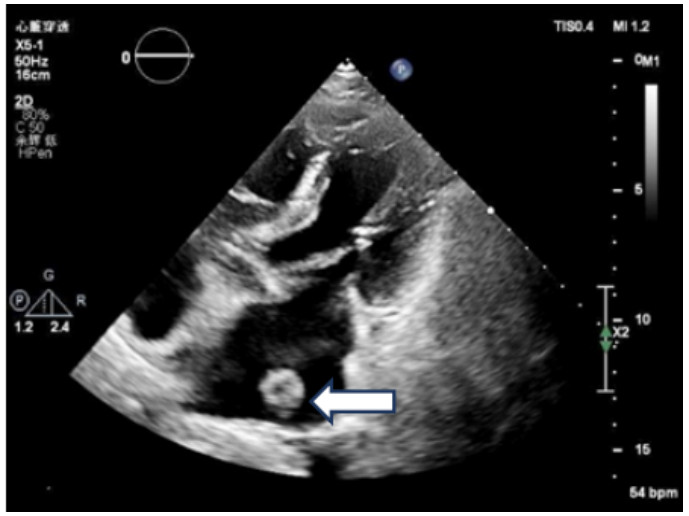

既往史:有高血压病史10年余,规律降压治疗,未监测血压。房颤病史2年余,2022年11月在本院超声心动图显示左心房见一不均质低回声团,位置随心动周期漂动(17 mm×16 mm)”(见图 1),左房前后径40 mm,左右径46 mm,上下径70 mm。LVEDD 39 mm,LVEF:60%。二尖瓣E峰0.92 m/s,最大压差3.39 mmHg(1 mmHg=0.133 kPa)。反流面积3.8 cm2,二尖瓣口频谱呈单峰。舒张期二尖瓣口前向血流,E < A,无舒张功能不全。进一步行经心脏超声造影提示:Flash后,左心室心腔内团块未见明显灌注(见图 2)。

| 注:Flash后,左心室心腔内团块影(箭头处)未见明显灌注 图 2 经患者肘静脉注射造影剂“声诺维”后行心脏超声造影(左心声学及心肌灌注) |